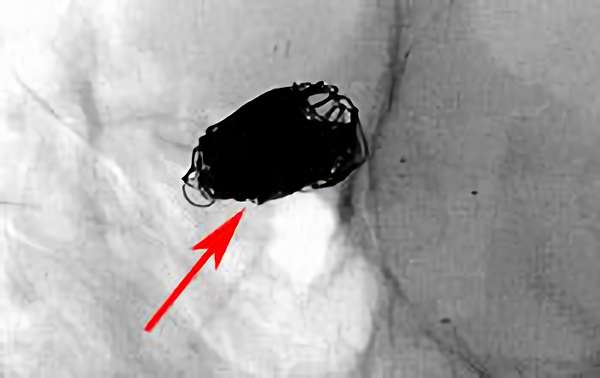

No.1631 手術中